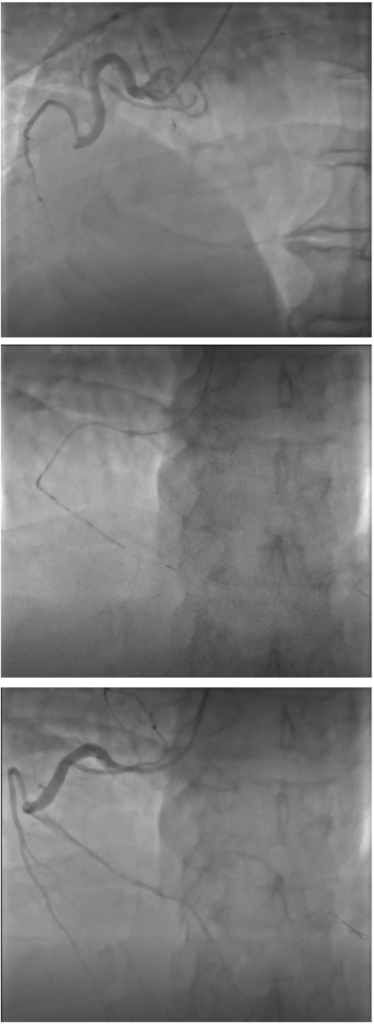

• 61-year-old male patient with cardiovascular risk factors of smoking and obesity admitted for anterior STEMI: Acute chest pain, hemodynamically stable, normal ejection fraction

• Coronary angio showed: Ectatic right coronary artery, Ectatic LAD occlusion with large thrombus burden (TIMI flow: 0, TIMI thrombus grade: 5)

• 2 enVast passes resulted in no residual thrombus debris and no sign of distal embolization with a final TIMI 3 flow

enVast™ 4.5 x 37 mm